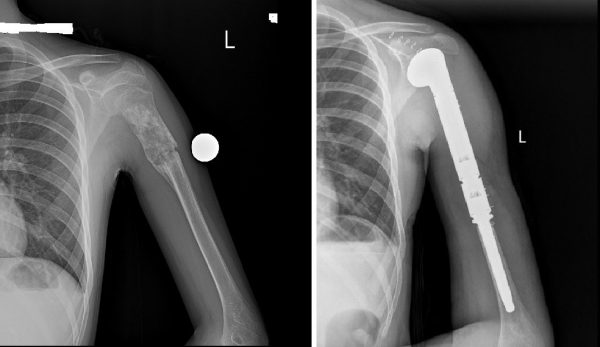

Улсын нэгдүгээр төв эмнэлгийн ХҮСҮСТ-ийн дарга М.Отгонбаяраар ахлуулсан үений мэс заслын баг Монгол Улсад анх удаа атгаал ясны дээд хэсгийн гуравны хоёрыг хамарсан том хэмжээний ясны хортой (osteosarcoma) хавдрын тохиолдолд хавдрыг бүхэлд нь авч мега-протез суулгах мэс заслыг амжилттай хийж гүйцэтгэлээ.

Ясны хавдрын үед том хэмжээний имплант суулгах мэс заслыг анх 2015 оноос эхлэн доод мөчдөд хийж эхэлсэн ба энэ удаагийнх нь дээд мөчид хийсэн анхны тохиолдол юм.

Уг эмчилгээний тохиолдлын мега-протез нь тухайн хүн өсөж томроход сунгагдах боломжтой тул дахин солих шаардлагагүй юм.